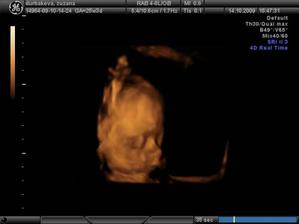

...a budeme traja :o)